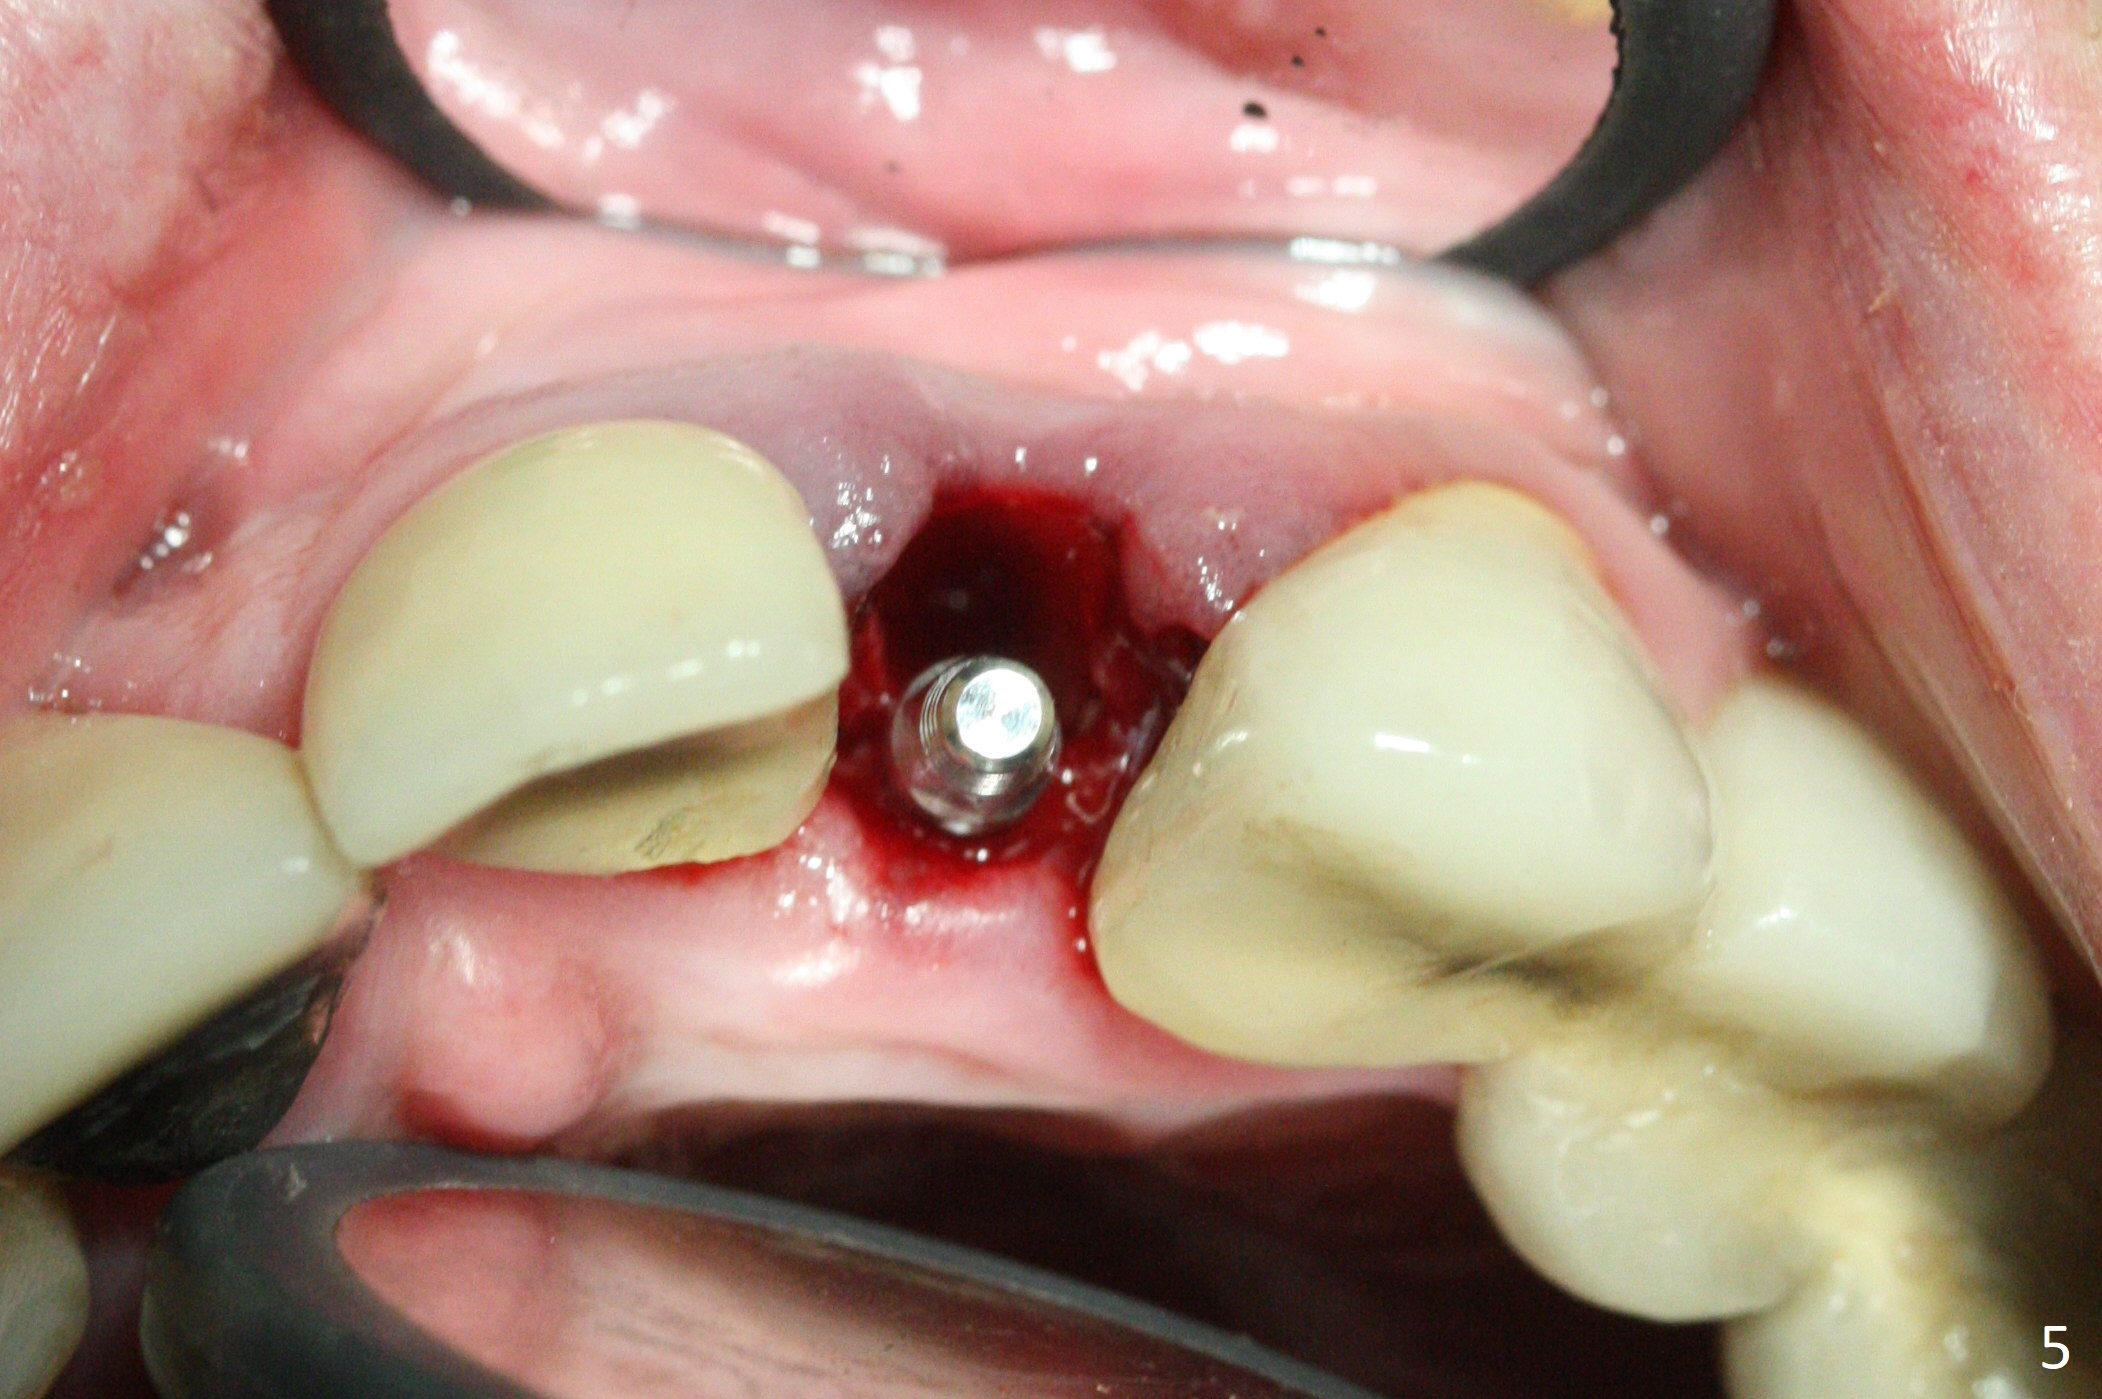

The tooth #10 fractures at the cervix, but is attached to the gingiva.  After extraction of the coronal portion of the tooth, the mesiodistal space palatally is found to be narrow (~4.7 mm, Fig.1).  It appears that a 1-piece implant is indicated because of the narrow mesiodistal space.  In fact the buccal plate of the socket is intact (Fig.2).  The initial osteotomy seems to be mesial (Fig.1) and is moved distal using Lindamann bur.  After sequential osteotomy, a 3x10 mm dummy implant is still mesial (Fig.4).  Following further distalization, a 3x14 mm implant is placed (Fig.5,6; <30 Ncm).  Vera Graft is placed in the remaining socket prior to provisional fabrication (Fig.6 *).  The socket outline disappears 7 months postop (Fig.7).  Panoramic X-ray is taken 1 year 3 month post cementation.